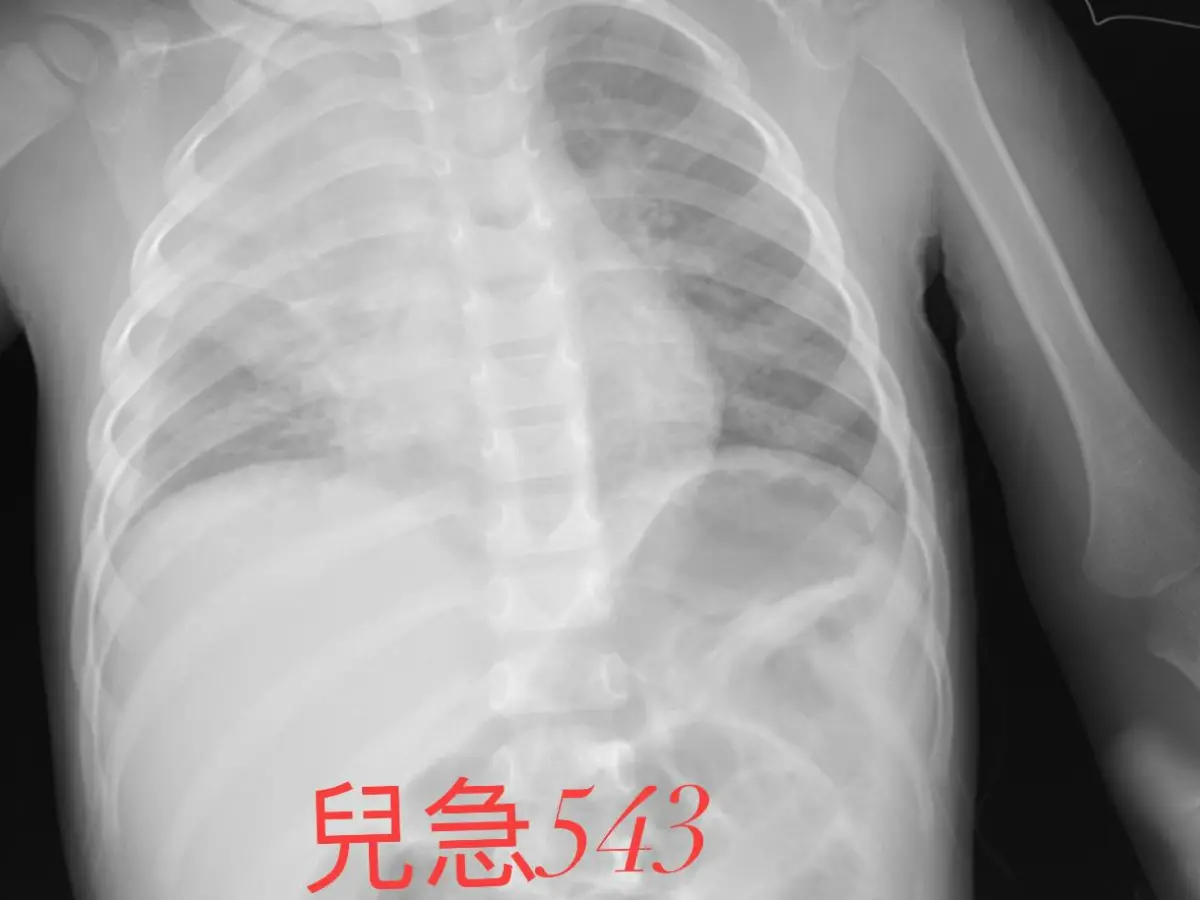

吳昌騰昨(26)在臉書粉專「來講兒科急診的543-吳昌騰醫師」示警,直言最近兒科急診病人真的多,因為現在有不少病毒正在流行,「尤其是RSV,有些小孩的症狀都十分嚴重」,可能會引發肺炎。

▲近來不少病毒正流行著,尤其是RSV,有些小孩症狀都很嚴重。圖為台大醫院急診室。(示意圖/記者徐銘穗攝) 「咳、痰、喘」吳昌騰說,當嬰幼兒感染了呼吸道融合病毒(RSV),只能用這三個字形容,會出現嚴重咳嗽的症狀,「氣管內、肺部的痰也會很多,喘息(Wheezing)很嚴重」。

吳昌騰還說,RSV不但會導致兒童發生嚴重的細支氣管炎、支氣管痙攣、肺炎和急性呼吸衰竭,「甚至RSV可導致病童重度呼吸暫停,嚴重時引起嬰兒猝死」,提醒第一線醫師及家長們要多加注意。